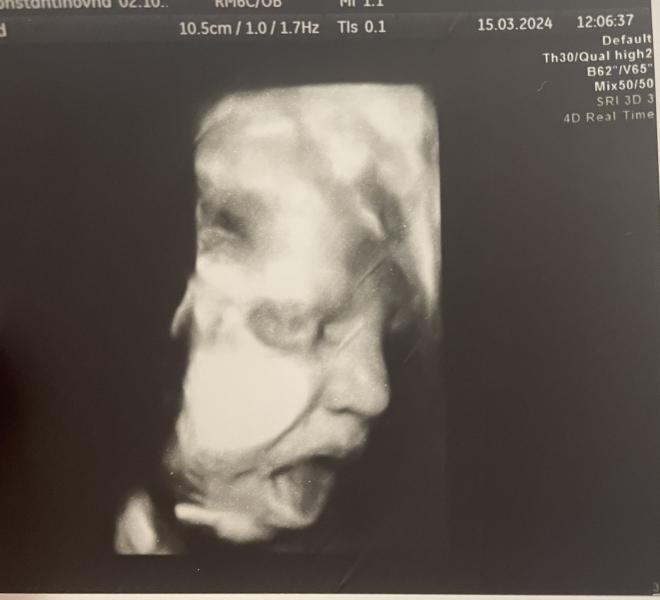

Боже современное узи это просто какое-то чудо.. вчера была на предродовом узи и врач показала сына в 4Д, мое сердце просто растаяло от папиного носа, хомячих щечек и маленьких пальчиков. А уж фото демонстрирующее вокальные возможности это вообще разрыв 😅

Поскорее бы с вами встретиться молодой человек ❤️